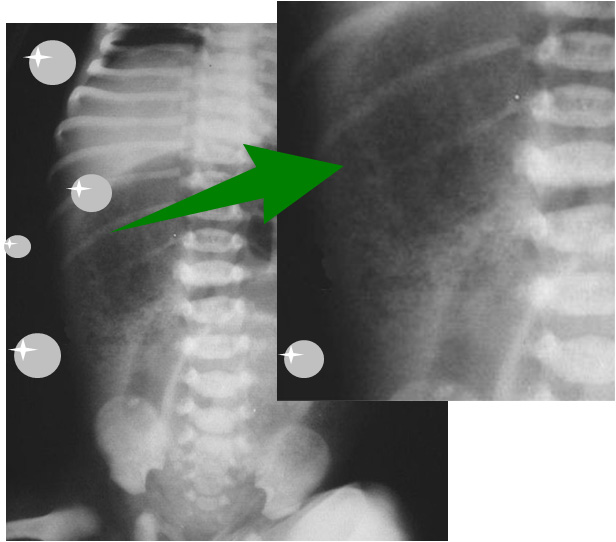

SIGNO DEL COLON CORTADO

Imagen de stop (flecha) en el luminograma del colon a nivel de la flexura esplénica, con el colon proximal distendido y descompresión del colon distal. Puede verse tanto en la radiografía simple de abdomen como en la TC y en el enema opaco, en pacientes con pancreatitis, pero también se ha visto en la trombosis vascular mesentérica y en la colitis isquémica.

Se debe a que el exudado inflamatorio de la pancreatitis infiltra el ligamento pericólico, provocando un espasmo o una estenosis mecánica en la flexura, al nivel donde el colon regresa al retroperitoneo. La distensión del colon transverso se debe a íleo adinámico local. Este signo (también llamado colon cut off ) puede simular una verdadera obstrucción.

El signo también se ha descrito en el carcinoma de colon, la enfermedad inflamatoria intestinal y la isquemia mesentérica.